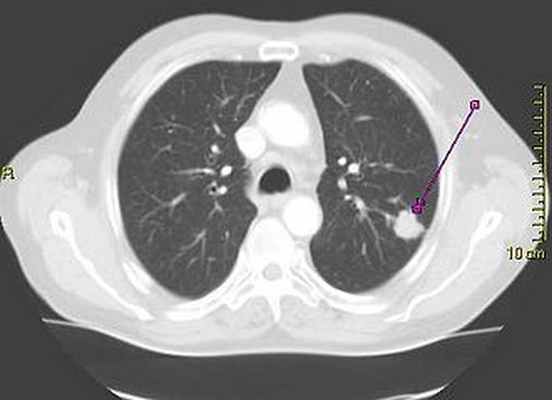

Солитарный лёгочный узел (одиночное периферическое образование) — в рентгенологии, периферическое образование в лёгочной ткани размером менее 3 см. Может быть случайной находкой на 0,2 % рентгенограмм грудной клетки [1] и около 1 % компьютерных томограмм [2] .

Солитарные лёгочные узлы следует отличать от инфильтратов, более крупных опухолей или образований с иными сопутствующими радиологическими симптомами. Солитарный лёгочный узел представляет собой единичный периферический очаг, со всех сторон окружённый лёгочной тканью, диаметром менее 3 см, не ассоциированный с пневмонией, ателектазом или лимфаденопатией [3] [4] .

Дифференцировать злокачественное периферическое образование от доброкачественного помогают некоторые особенности. Учитывается размер образования: чем оно меньше, тем меньше риск злокачественности. Доброкачественные образования обычно имеют чёткие контуры, злокачественные имеют неравномерные, местами нечёткие границы или дольчатую структуру [4] . При наличии в образовании полости, имеет значение толщина её стенок: чем тоньше стенка, тем более вероятна его доброкачественная природа, и наоборот (наиболее достоверна толщина стенок менее 4 мм или более 16 мм, соответственно) [4] . При раке лёгкого, полость в толще очага обусловлена некрозом (распадом) или вторичным абсцедированием. Если на фоне очага визуализируются воздушные полоски бронхов (воздушная бронхограмма), следует заподозрить бронхиолоальвеолярный рак.

Зачастую солитарные лёгочные узлы содержат кальцинаты. Существуют характерные паттерны обызвествления, например, обызвествление при гамартоме имеет вид «попкорна» [1] . Одиночные лёгочные узлы с денситометрическими показателями мене 15 HU при компьютерной томографии более вероятно имеют доброкачественный характер, чем узлы с денситометрическими показателями более 25 HU. Жировая ткань в структуре гамартом будет иметь достоверно отрицательные значения по шкале Хаунсфилда.

Солитарный легочный узел – это образование диаметром < 3 см, которое полностью окружено паренхимой легкого (т.е. не прилежит к корню легкого, средостению или плевре), не связано с ателектазом или плевральным выпотом. (Оценка опухоли средостения Медиастинальные новообразования Медиастинальные новообразования возникают из-за разнообразных кист и опухолей; возможные причины образований зависят от возраста пациента и локализации образования (переднее, среднее или заднее. Прочитайте дополнительные сведения рассматривается подробнее в других разделах).

(а) У женщины 48 лет без жалоб при рентгенографии органов грудной клетки в ПП проекции в базальных отделах правого легкого определяется неоднородный узелок с нечетким контуром.

(б) У этой же пациентки при КТ с контрастным усилением в нижней доле правого легкого визуализируется узелок с дольчатым, умеренно спикулообразным контуром, содержащий гиподенсные участки, которые могут соответствовать полостям или поперечным срезам просветов бронхов. При операции была выявлена инвазивная преимущественно ацинарная аденокарцинома.